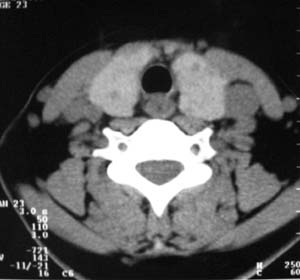

以下是引用zsl6918在2007-8-27 14:40:00的发言:[br]双侧甲状腺多发性低密度占位,边界清晰,密度欠均匀,尤以左侧明显,与周围组织分解清,考虑多发性腺瘤可能性大,不除外结节性甲状腺肿

以下是引用liaizhi在2007-8-27 15:20:00的发言:[br]双侧甲状腺散在多个囊性第密度影,左侧最大一个病灶与正常甲状腺分界尚可,气管受压稍右移。考虑甲状腺瘤的可能性大。